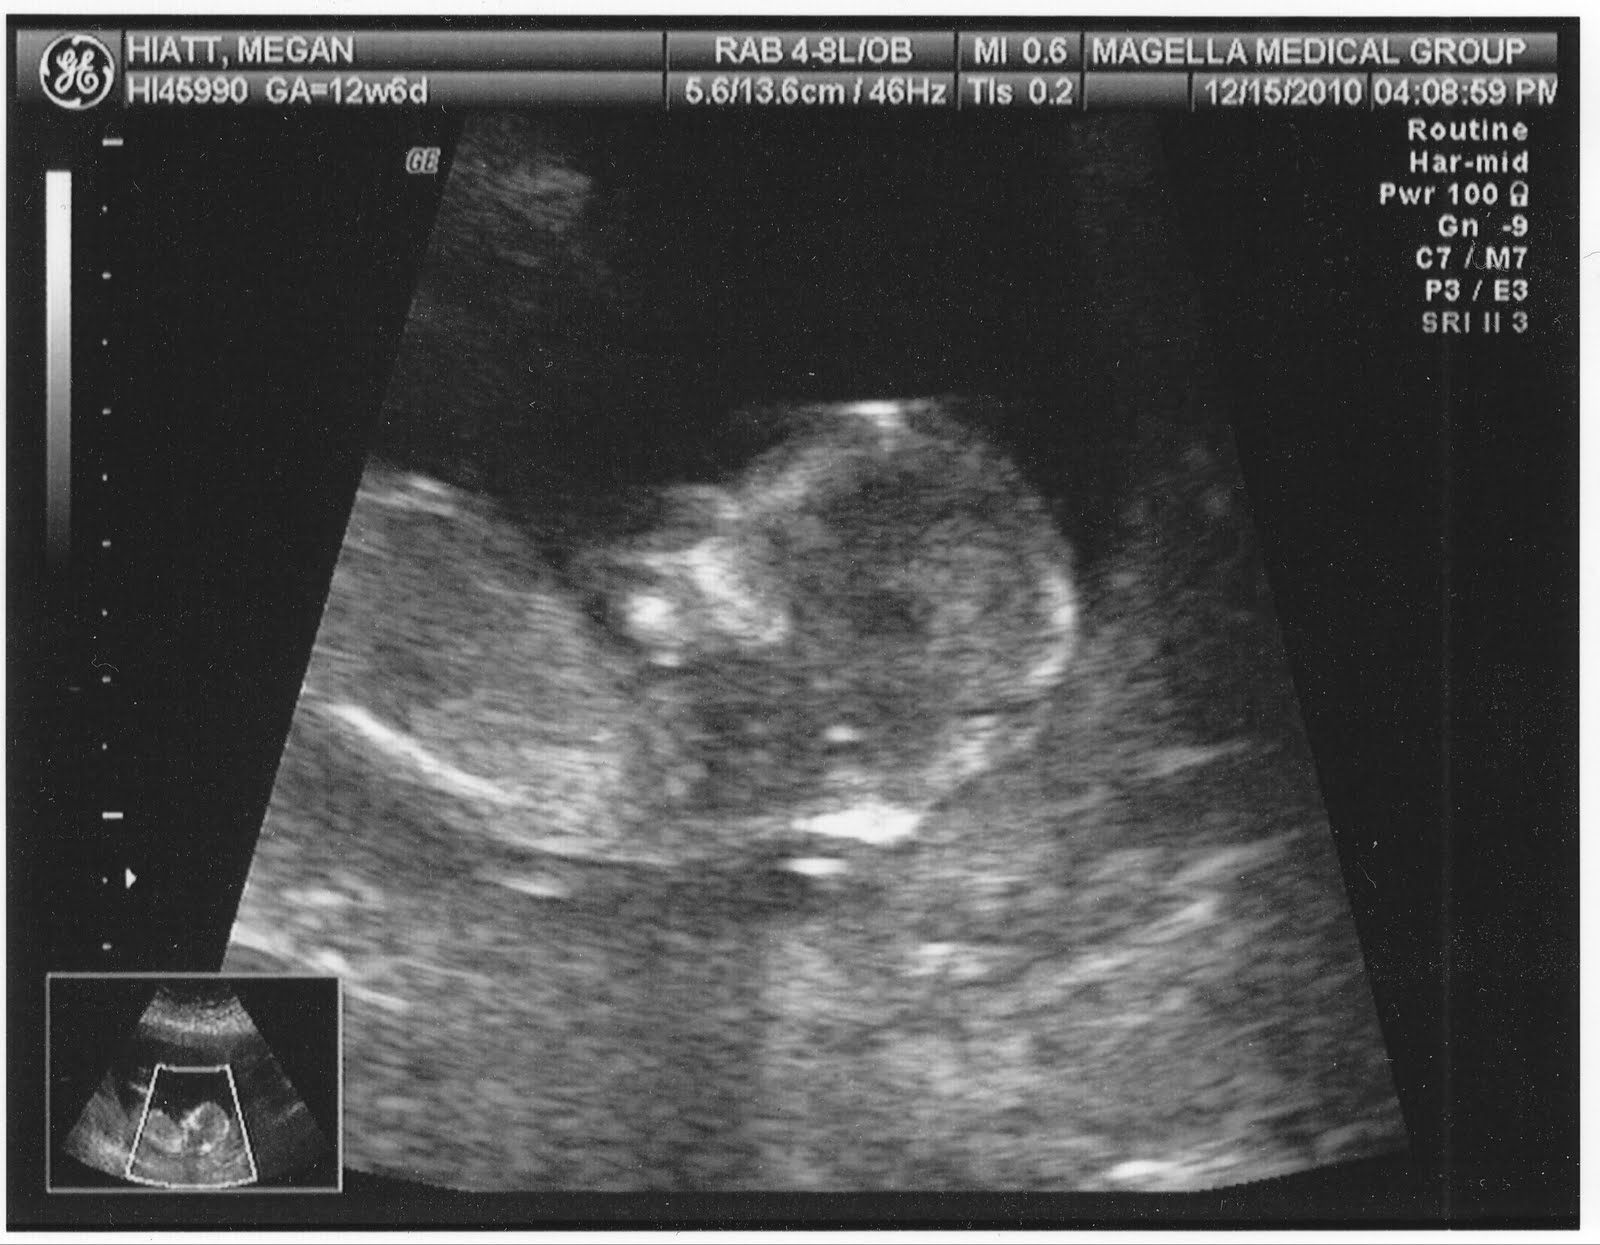

Ultrasound week. 13 week ultrasound

The Spamdrew Family: 13 Week Ultrasound